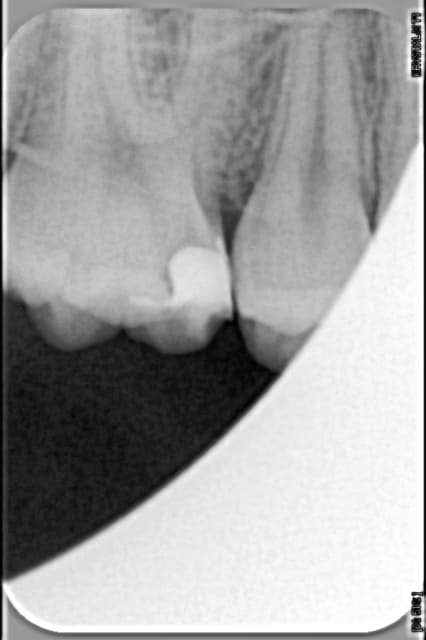

Petit patient de 10 ans, je curete sa carie en mésial de 16, la cavité m'a l'air impec, je passe la curette manuelle pour bien être sûr, je passe la sonde et tout est dur, la sonde crisse sur la dentine, je fais mon compo bien au sec (sans digue, ok mais au sec quand même)

Je suis dans une période de remise en question (où travailler? avec qui? comment? bla bla bla) et je cherche à savoir ce que je vaux vraiment, donc je fais un cliché après avoir fait mon compo pour voir si je bosse bien et j'obtiens la radio ci dessous.

Mon ego en prend un coup! Moi qui croyait avoir bien fait, j'obtiens un gros liseré radioclair sous mon compo, pourtant :

- je pense que mon curetage était vraiment correct (couleur, dureté de la dentine)

- il n'y avait pas de résidu d'adhésif au fond de la cavité après sa polymérisation

- je pense avoir bien foulé mon compo jusqu’au fond de la cavité

- le compo n'était pas décollé

Bref, je ne vois pas pourquoi j'ai eu ça

@jeff13 : j'ai vérifié si mon adhésif était radio opaque en faisant un cliché d'un peu d'adhésif polymérisé sur la protection du capteur radio, et il n'est pas du tout radio opaque, ce qui est une 1e hypothèse concernant la radioclarté sous mon compo! mais je pense avoir vraiment bien séché après l'avoir appliqué

@cyber_quenottes : l'artefact radio pourquoi pas, il faudrait que je fasse des radios sous mes amalgames pour voir si j'ai la même chose alors

@clemsdent : oui effectivement, en modifiant les filtres sur la radio on peut faire disparaître la radioclarté, je l'avais bien remarqué mais je me posais quand même la question de savoir pourquoi il était là avec certains filtres!